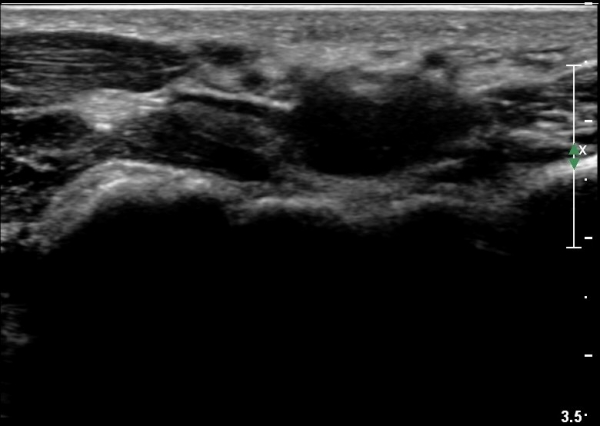

¼Õ¸ñÀÇ È¾´Ü¸é°Ë»ç¿¡¼­ Á¤Á߽ŰæÀÇ ºÎÁ¾ µî ƯÀÌ ¼Ò°ßÀÌ º¸ÀÌÁö ¾Ê´Â´Ù(»çÁø 1).